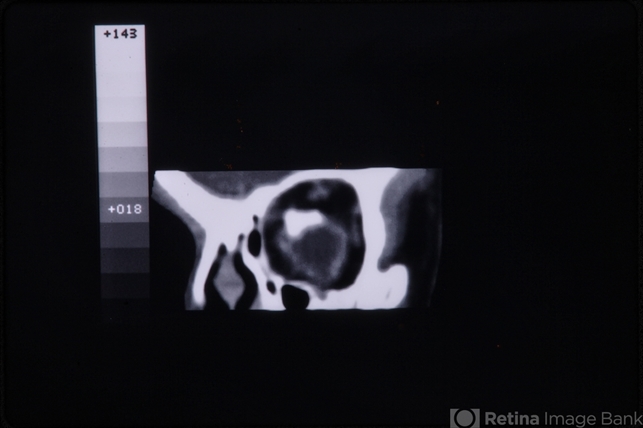

- linear nevus sebaceous syndrome, CT scan

- CT scan of linear nevus sebaceous syndrome.